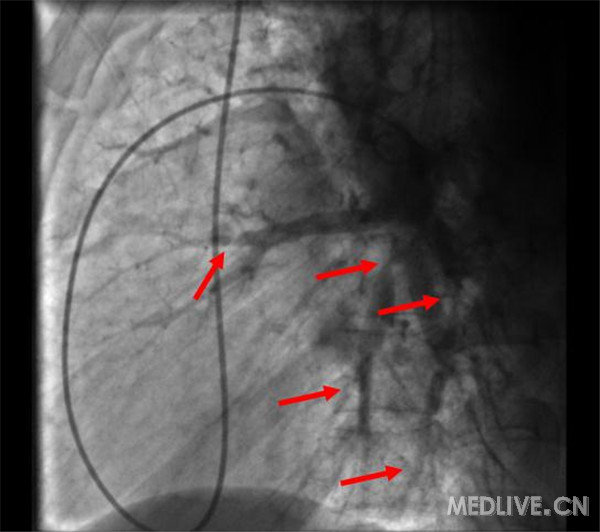

肺动脉造影示:左、右肺动脉扩张,管壁僵硬,右肺下叶动脉开口闭塞,远端血流灌注缺失;右肺上叶前段及中叶分支可见多发狭窄,远端血流灌注呈节段性减低(图2);左肺下叶内前基底段开口重度狭窄,余基底段动脉亚段以下分支可见多发狭窄性病变,远端血流灌注明显减低(图3)。